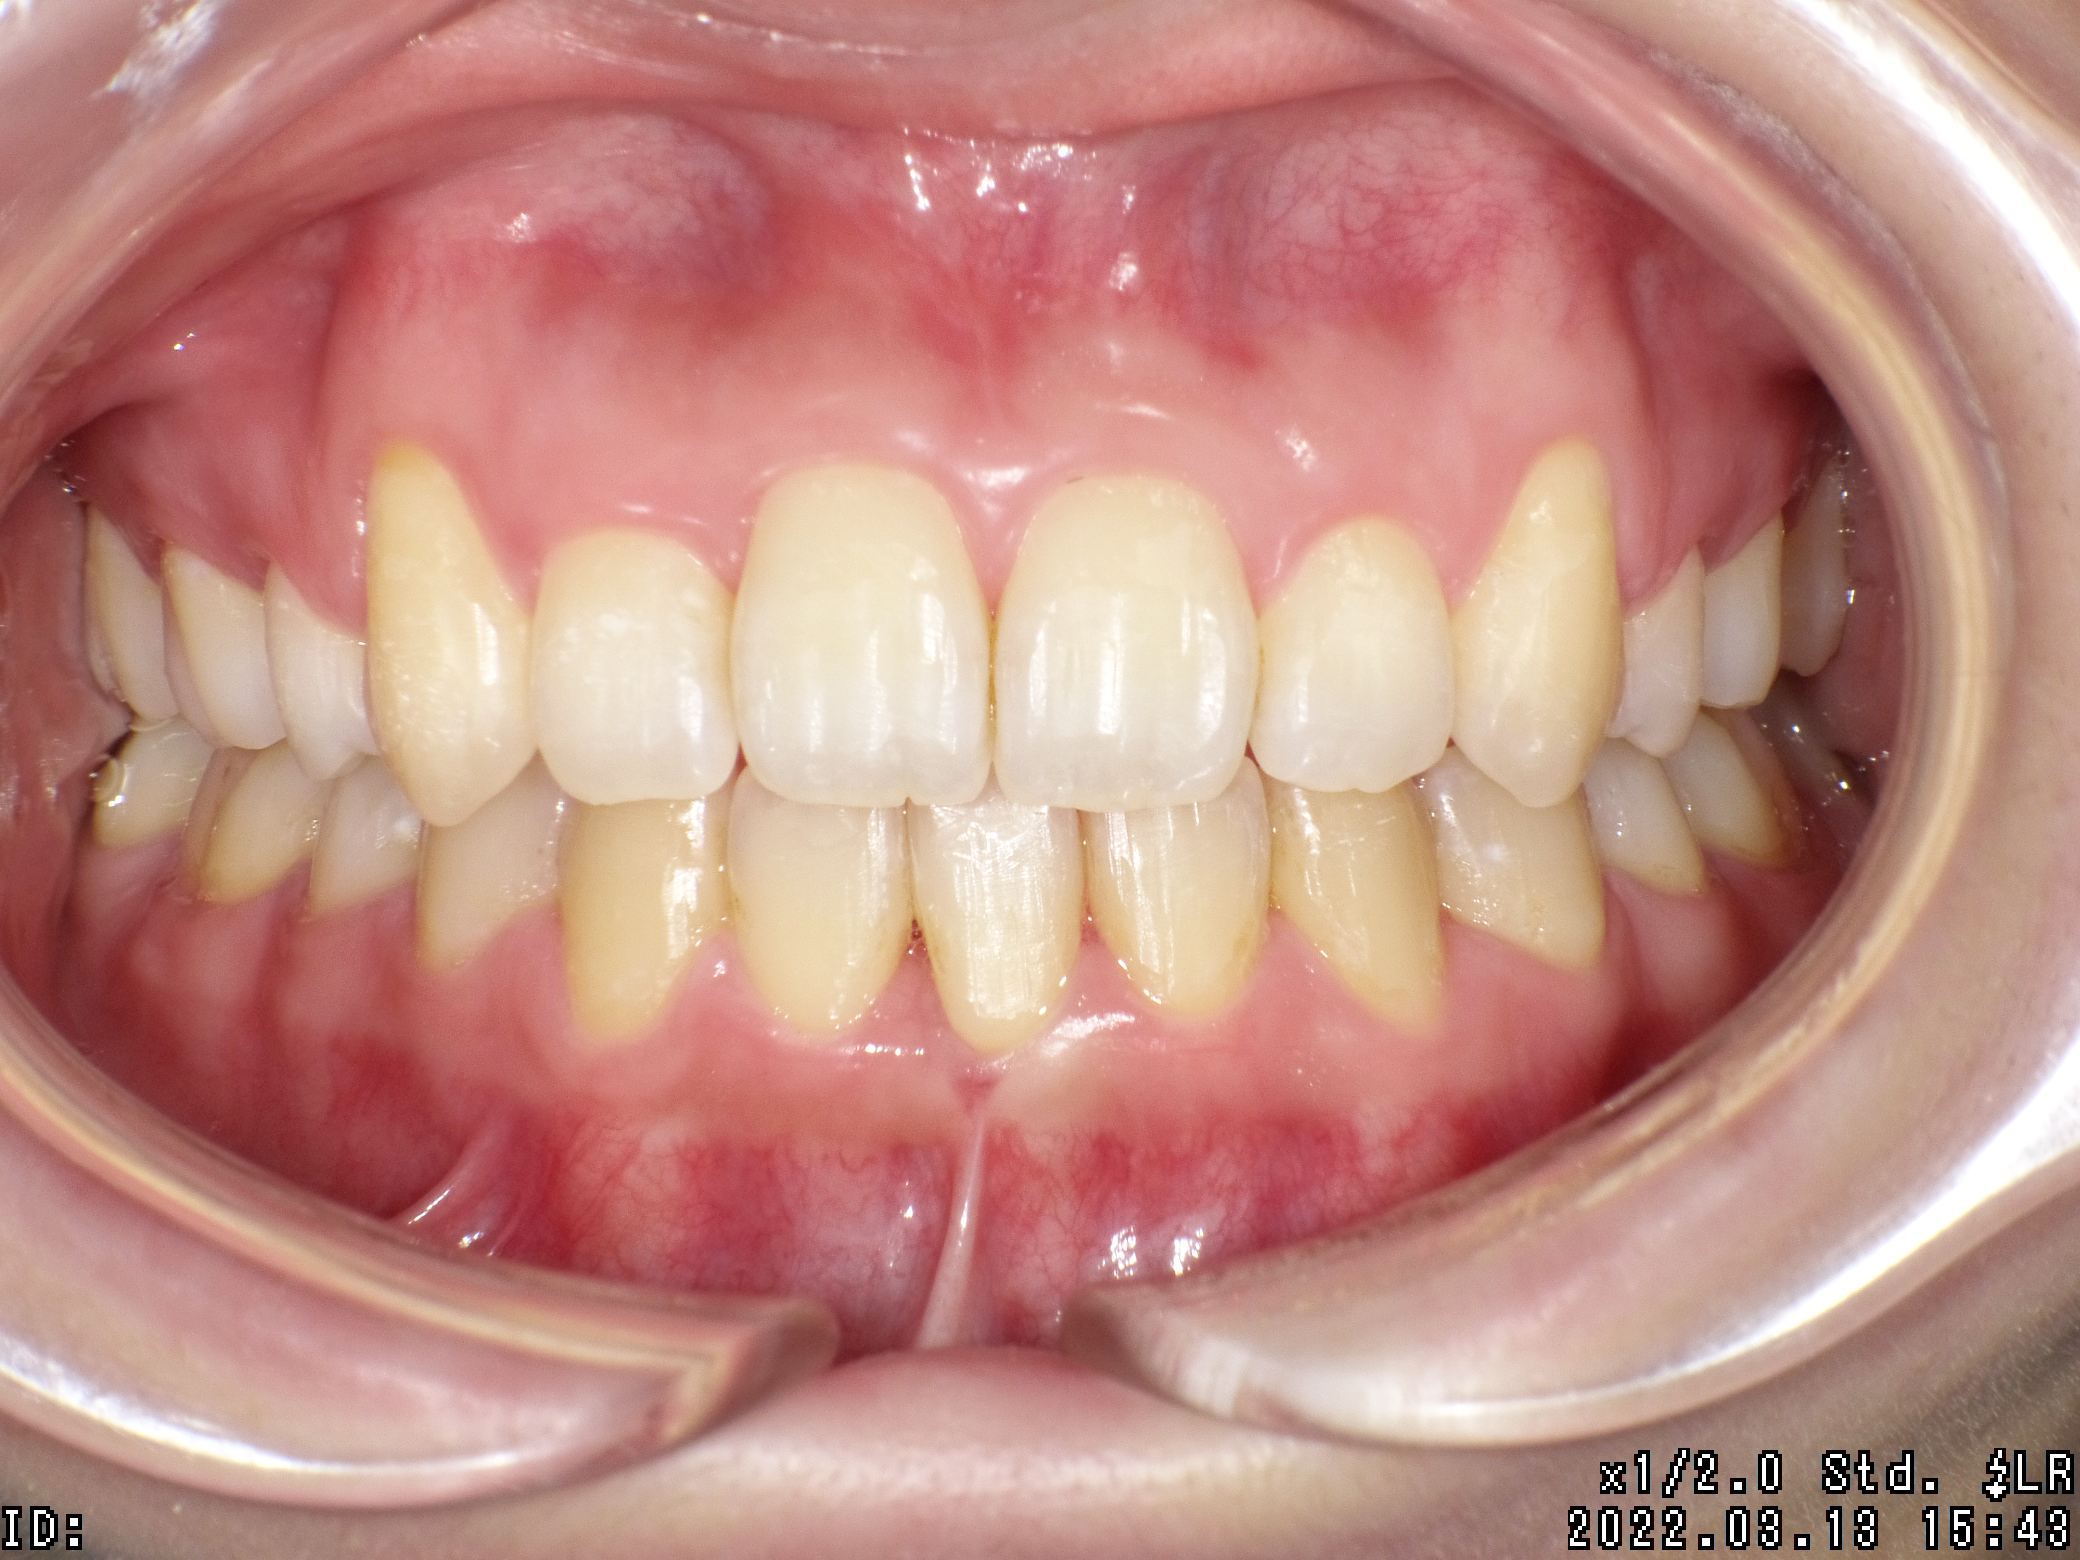

| 治療期間 | 2020年11月15日 〜2022年3月13日 |

|---|---|

| 治療費用 | 約770,000円 |

| 抜歯有無 | 抜歯あり |

| 矯正箇所 | クリアブラケット矯正 |